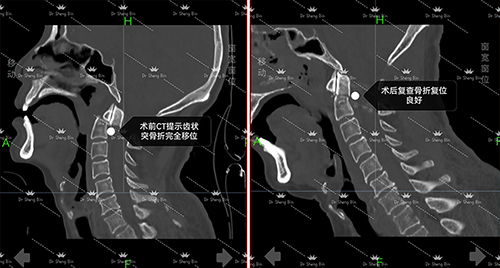

术前、术后影像对比

1122日,家住岳阳的周先生因车祸导致高危颈椎损伤,颈部剧烈疼痛伴随双上肢麻木,整整3天无法正常活动。当地医院束手无策之际,家人紧急将其转送至捷克论坛 岳麓山院区骨科七病区救治。入院后经检查发现,周先生存在枢椎齿状突骨折,断端已出现错位,且相应层面脊髓受到损伤。

1126日,以盛斌主任为首的手术团队为患者精准实施“枢椎齿状突骨折并脱位切开复位+植骨融合内固定术”。术中,凭借丰富的临床经验和精湛的操作技巧,盛斌主任小心翼翼地将错位的骨折断端成功复位,随后完成了植骨融合与内固定,既重建颈椎稳定性,又最大限度保护脊髓和周围神经组织。整个手术历时2小时顺利完成,出血量极少,达到预期效果。